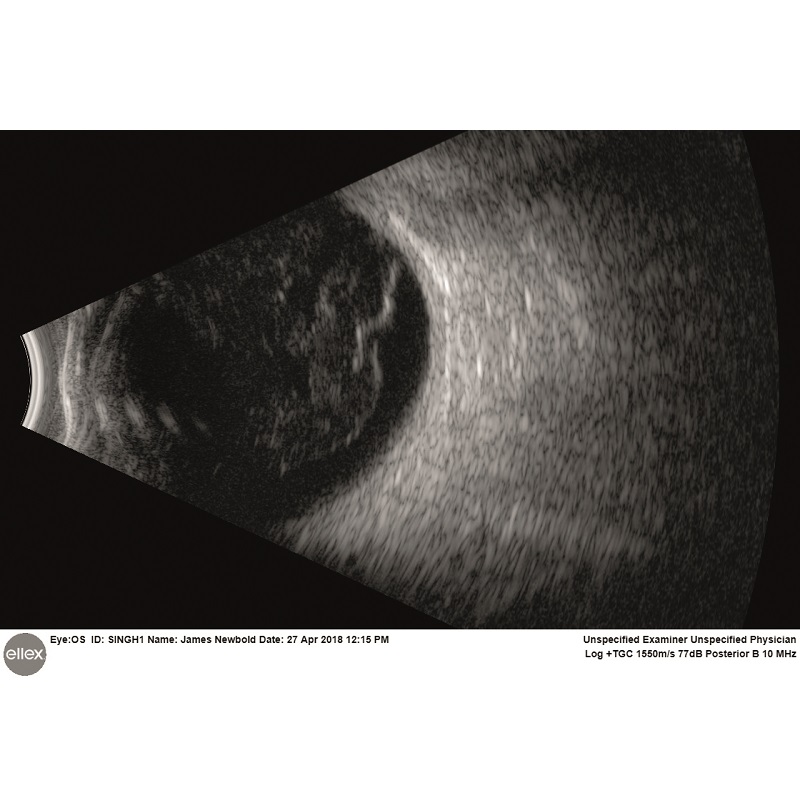

Intuicyjna platforma ultrasonograficzna Eye One obejmuje szeroki zakres trybów skanowania zarówno w odcinku tylnym, jak i przednim. Sprzęt jest w stanie wykryć najsubtelniejsze echa ciała szklistego, oferując niezwykłą dokładność diagnozy siatkówki, naczyniówki czy twardówki. W przednim trybie szerokiego pola Eye One umożliwia oglądanie całego segmentu oka w celu zidentyfikowania przyczyn choroby związanej z jaskrą oraz dokładnego i spójnego pomiaru kluczowych parametrów kąta.

Prezentacja A (tak/nie): Tak

Prezentacja B (tak/nie): Tak

UMB (tak/nie): Tak